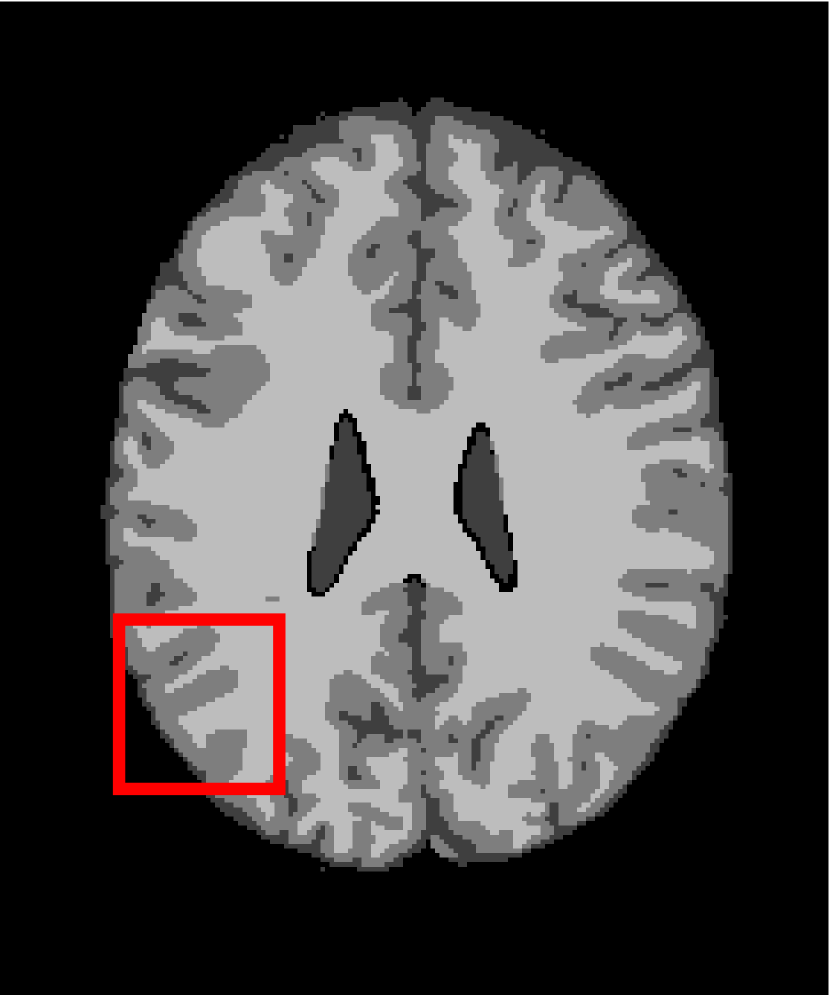

Next, we representatively segment five medical images from BrianWeb. They are represented as five slices in the axial plane with a sequence of 70, 80, 90, 100 and 110, which are generated by T1 modality with slice thickness of 1mm resolution, 9% noise and 20% intensity non-uniformity. Here, we set c=4𝑐4c=4 for all cases. The comparison between WRFCM and its peers are shown in Fig. 9 and Table II. The best values are in bold.

Figure 9: Segmentation results on five medical images. The parameter: ϕ=5.35italic-ϕ5.35\phi=5.35. From top to bottom: noisy images, ground truth, and results of FCM_S1, FCM_S2, FLICM, KWFLICM, FRFCM, WFCM, DSFCM_N, and WRFCM.

By a view of the marked red square in Fig. 9, we find that FCM_S1, FCM_S2, FLICM, KWFLICM and DSFCM_N are vulnerable to noise and intensity non-uniformity. They give rise to the change of topological shapes to some extent. Unlike them, FRFCM and WFCM achieve sufficient noise removal. However, they produce overly smooth contours. Compared with its seven peers, WRFCM can not only suppress noise adequately but also acquire accurate contours. Moreover, it yields the visual result closer to ground truth than its peers. As Table II shows, WRFCM obtains optimal SA, SDS and MCC results for all five medical images. As a conclusion, it outperforms its peers visually and quantitatively.